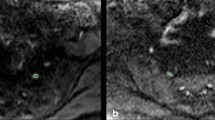

T2 mapping of the distal sciatic nerve and placement of the region of interest (ROI). Representative axial slices of the two-dimensional (2D) T2-weighted DIXON turbo spin echo (TSE) sequence and the T2 map derived from the three-dimensional (3D) T2-prepared TSE sequence in a healthy volunteer (lower thigh region of the left leg). The red arrow points to the lower sciatic nerve in the 2D T2-weighted DIXON TSE sequence (a), the red square encloses the nerve in the T2 map (b). Polygonal ROIs were placed in the three consecutive axial slices depicting the distal sciatic nerve, with ROIs contouring the whole sciatic nerve caliber without the inclusion of surrounding soft tissue or blood vessels (c). The 2D T2-weighted DIXON TSE sequence is scaled with arbitrary units (a.u.), T2 values were extracted in ms. The same approach of ROI placement was followed for the measurements of T2 values in T2 maps derived from a 2D multi-echo spin-echo (MESE) sequence

Comparison of T2 maps of the distal sciatic nerve. Comparison between the two-dimensional (2D) T2-weighted DIXON turbo spin echo (TSE) sequence [scaled with arbitrary units (a.u.)], the T2 map derived from the 2D multi-echo spin-echo (MESE) sequence (T2 map MESE), and the T2 map derived from the three-dimensional (3D) T2-prepared TSE sequence (T2 map T2Prep 3D TSE) in a healthy volunteer (lower thigh region of the left leg). Note the higher T2 values (in ms) in the T2 maps of the 2D MESE sequence for structures with fat (particularly the thigh musculature) in comparison to the T2 maps of the 3D T2-prepared TSE sequence

First, the distal sciatic nerve was carefully identified on axial slices of the color-coded T2 maps, co-registered to uncolored anatomical images of the 2D T2-weighted DIXON TSE sequence that served as reference for enhanced structural interpretability. Then polygonal regions of interest (ROIs) were manually placed in the three consecutive slices directly above the nerve bifurcation of the sciatic nerve, thus above the split into tibial and common peroneal trunks (Figs. 1, 2) [4]. Each of these ROIs contoured the whole nerve caliber whilst inclusion of surrounding soft tissue or blood vessels was avoided. T2 values were separately extracted from the three consecutive ROIs drawn in the T2 maps derived from the 3D T2-prepared TSE sequence and the 2D MESE sequence, if available (Figs. 1,2). The approach of ROI drawing was the same in healthy subjects and patients and for both sides, respectively.